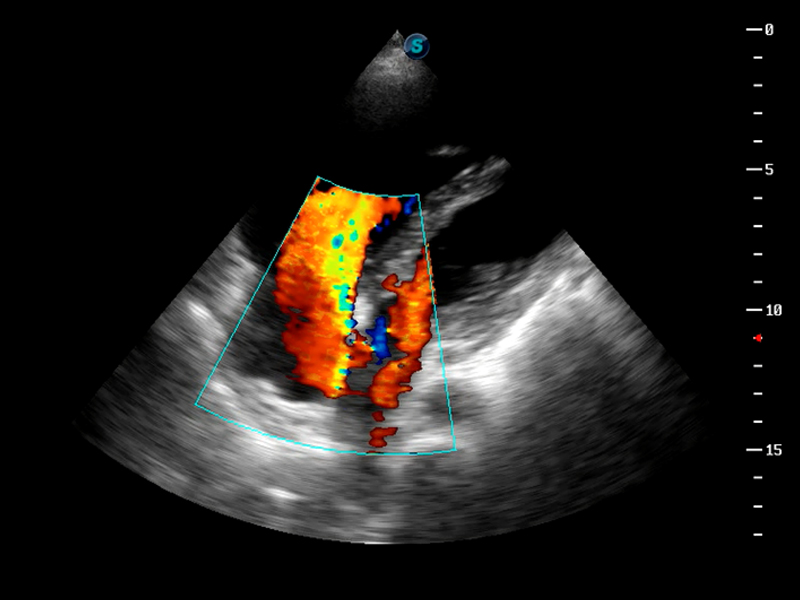

S9便携式彩色多普勒超声诊断仪是竞技宝(JJB)官方网站研发的高端便携彩超设备,外观设计新颖、产品性能卓越。S9在便携超声领域采用了突破传统的触摸屏交互设计,并以先进的软件硬件技术和设计理念,为您带来清晰的图像质量、稳定的工作性能和便捷的操作体验。

μ-Scan微米成像

脉冲反相谐波成像

TDI组织多普勒成像

AutoC智能血流追踪